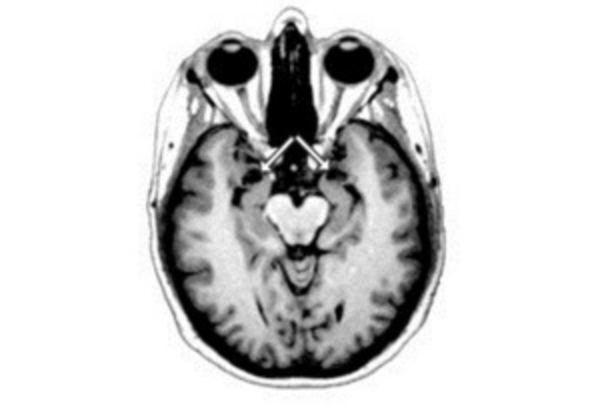

Ранее американские нейробиологи заявили, что силу боли, которую испытывает человек, можно измерить по томограммам некоторых областей мозга.